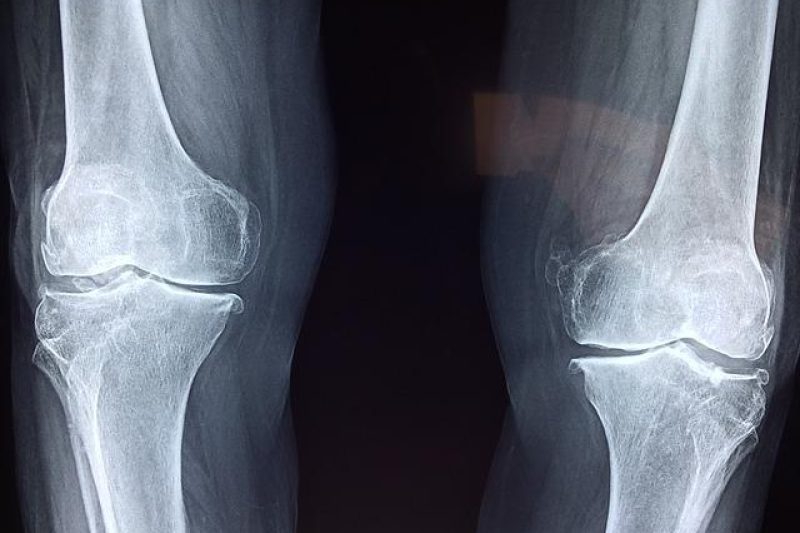

Knees that creak, ache, or outright hurt limit your daily activity and ability to do all the fun things you enjoy. Don’t let a bum knee hold you back. …